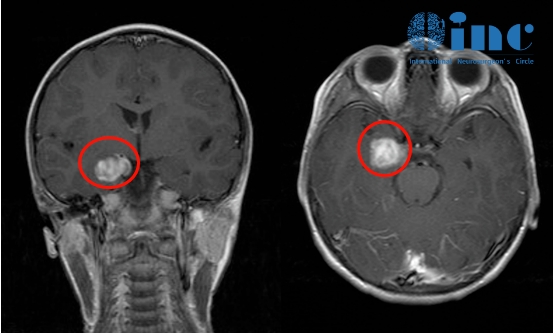

一名11岁男孩因梗阻性脑积水出现头痛和复视。脑部MRI显示四叠体板处有一个脑内部分对比增强的病变,从小脑延伸至松果体,并导致脑积水。对病变进行了次全切除,男孩被确诊为间变性神经节细...